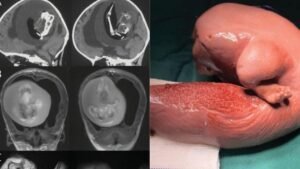

Uma menina de um ano de idade teve o feto de sua irmã gêmea removido do seu crânio em procedimento cirúrgico na China. O caso,